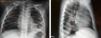

Niño de 3 años, valorado en urgencias por fiebre y tos de una semana de evolución, con buen estado general. A la auscultación pulmonar destacaba hipoventilación y crepitantes en base izquierda, mostrando la radiografía de tórax aumento de densidad en lóbulo inferior izquierdo con imágenes hidroaéreas en su interior y pinzamiento del seno costo-diafragmático ipsilateral (fig. 1). El paciente no disponía de radiografías previas; se planteó diagnóstico diferencial entre neumonía complicada con necrosis y derrame paraneumónico versus hernia diafragmática congénita con contenido intestinal en tórax. Se solicitó tomografía computarizada torácica, que demostró integridad diafragmática, identificando imagen compatible con neumonía cavitada sin derrame pleural (fig. 2). Tras antibioterapia endovenosa con cefotaxima y clindamicina presentó normalización radiológica a los 2 meses del alta (fig. 3).